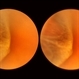

- retinal break, meridional fold, ora serrata

- This is the same case as seen in the previous photograph but showing an area just below the lower end of the dialysis. It shows a congenital meridional fold at the 2 o’clock meridian with a retinal break at the posterior end possibly caused by the direct injury described previously.